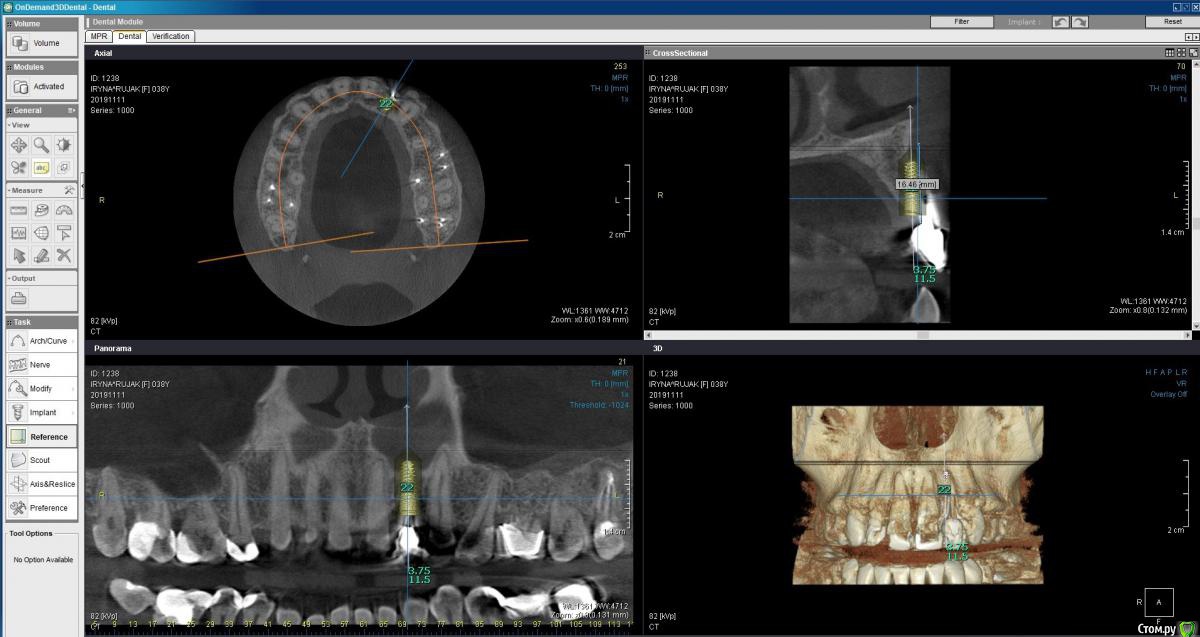

Пациентка 37 лет, не курит, соматически здорова. Частое выпадение ЛШКВ с коронкой. Диагностирована  фрактура вестибулярной стенки кореня зуба 22. Линия улыбки высокая. Биотип толстый.  Отсутствие вестибулярной пластинки, карман 8мм без ексудата.  Латеротрузия через 22.

Какая стратегия предпочтительней удаление корня 22, НКР, времянка понтик, потом имплантация с правельним наклоном. Или одномоментно с вестибулярным уклоном и в будущем  инд.абатмени+цементная фиксация.

2 вариант смело,через навигацию